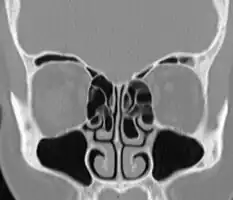

A concha bullosa is a pneumatized (air-filled) cavity within a nasal concha, also known as a turbinate.[1]

Bullosa refers to the air-filled cavity within the turbinate.[1] It is a normal anatomic variant seen in up to half the population. Occasionally, a large concha bullosa may cause it to bulge sufficiently to obstruct the opening of an adjacent sinus, possibly leading to recurrent sinusitis[1] and various head pains related to areas innervated by the trigeminal nerve.[2] In such a case the turbinate can be reduced in size by endoscopic nasal surgery (turbinectomy). The presence of a concha bullosa is often associated with deviation of the nasal septum toward the opposite side of the nasal cavity.[3]